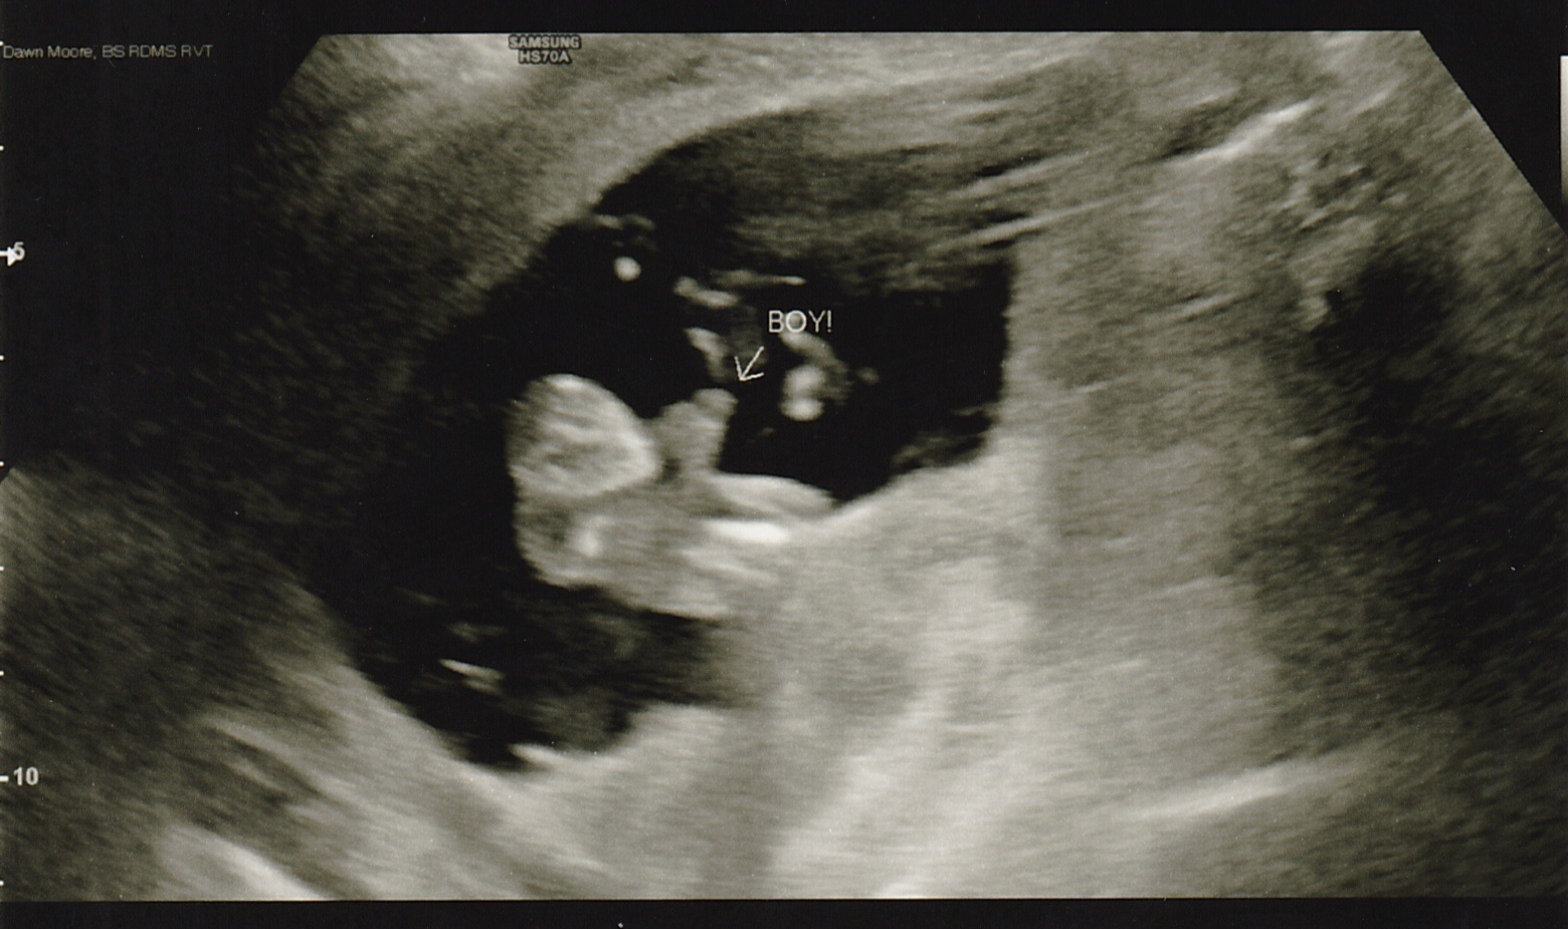

and NIPT results say BOY!